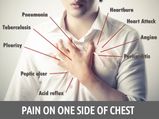

Reasons For Pain On One Side Of Chest

Reasons For Pain On One Side Of Chest -